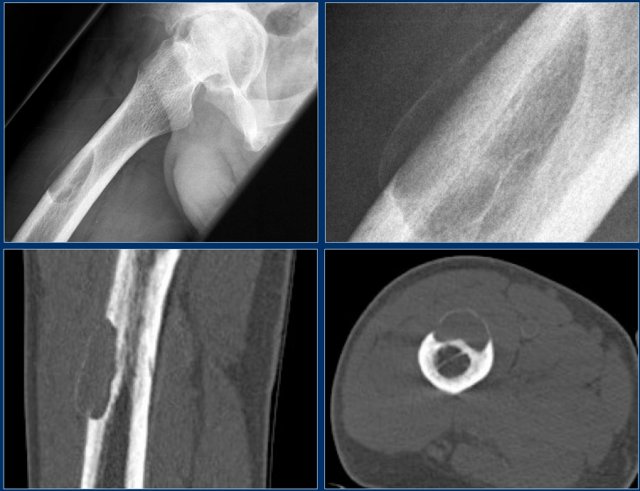

ABC (8)

On the left another ABC, located in the distal femur.

The plain radiograph shows a layered periosteal reaction and Codman triangle in direct relationship to an expansile lytic lesion with a thin peripheral bone shell.

CT also reveals the subperiosteal origin of the lesion with secondary involvement of the cortical bone.

Axial T2-weighted image with fatsat and contrast enhanced T1-weighted image with fat sat show multiple fluid-fluid levels with rim enhancement of the cavities filled with blood.

This is typical for an aneurysmal bone cyst.